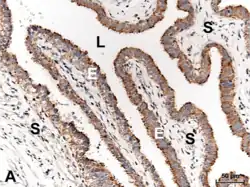

Histología

La pared de las trompas en su cara interna (luminal) es compleja. La mucosa está dispuesta sobre pliegues longitudinales denominados "plicas".

La estructura histológica varía en los diferentes segmentos, lo que permite una funcionalidad adaptada en cada uno. Se observan tres capas tisulares diferentes mucosa (endosalpinge), muscular (miosalpinge) y serosa, sus proporciones varían en los distintos segmentos.[12][13]

Internamente, cada oviducto está cubierto de una mucosa con pliegues ("plicas"), con un epitelio cilíndrico pseudoestratificado con células ciliadas, células caliciformes y células no ciliadas intercalares (o peg). Las células epiteliales descansan sobre una lámina basal y una lámina propia conjuntiva laxa subyacente.

La capa media contiene músculo liso, donde se puede distinguir una capa circular interna y otra longitudinal externa.

La capa más externa consiste en la serosa de epitelio simple plano, con tejido conectivo subyacente donde se pueden observar grandes vasos sanguíneos y nervios.